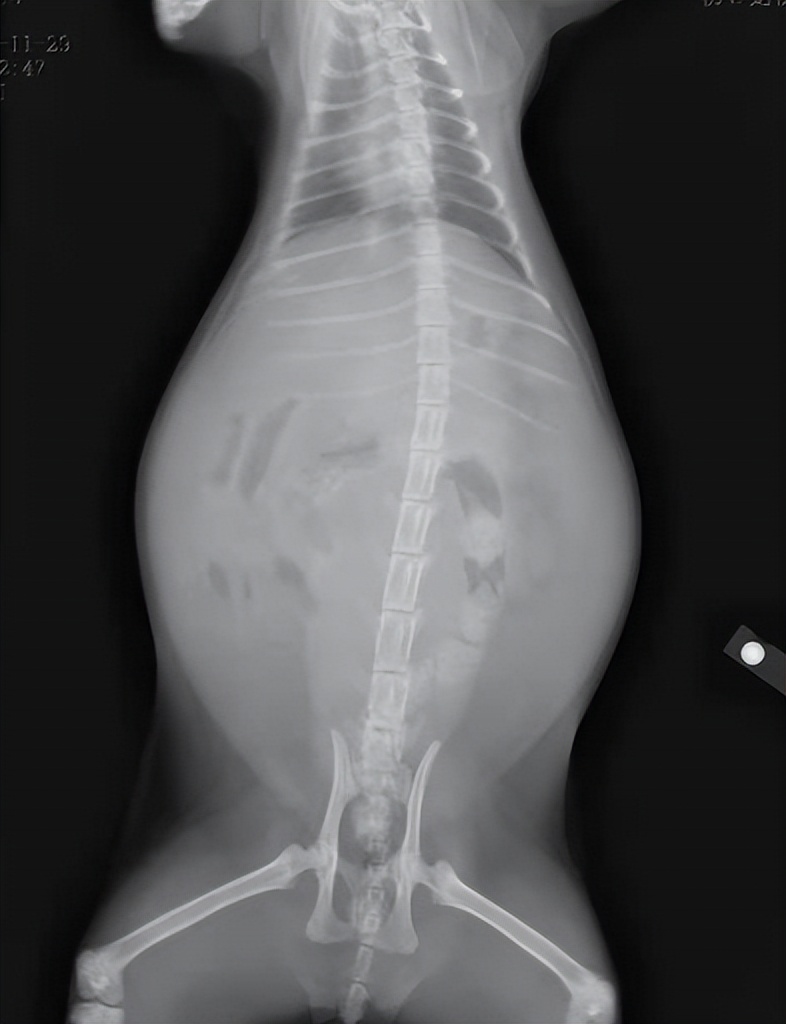

这只患病猫咪的胸腔因为充满积液,从而腹部肿胀